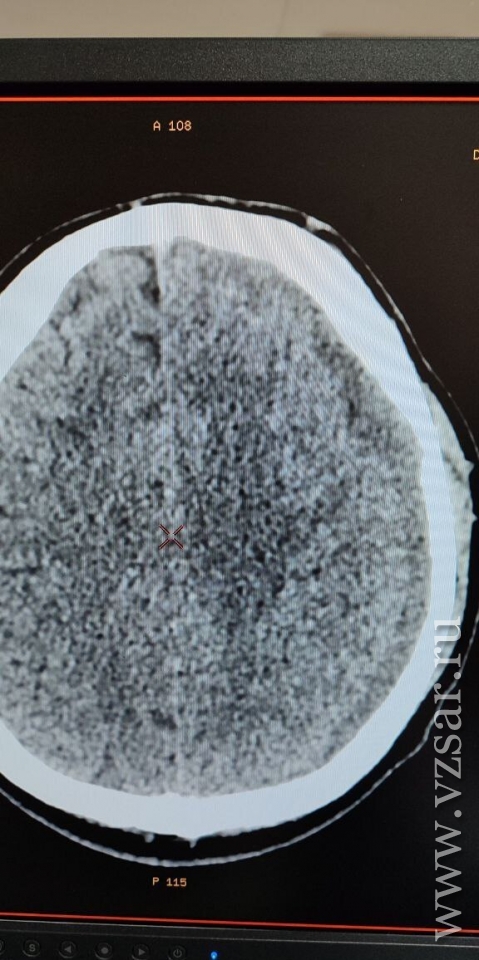

Обследование показало очаги контузии обоих полушарий и небольшого объема гематому слева, которая смещала структуру мозга.

Медики успешно выполнила эндоваскулярную эмболизацию средней оболочечной артерии слева микрочастицами. Уже через 4 суток исследование показало значительное уменьшение гематомы - на 20%, а смещение мозга уменьшилось вдвое.